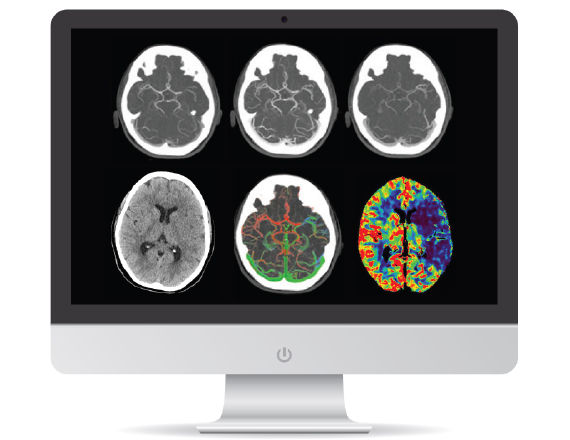

A patient with suspected TIA or stroke receives a general and neurological examination followed by diagnostic brain imaging, performed immediately on arrival so that treatment can be started promptly. 3 Optimal scanning coupled with workflow applications and protocols designed for stroke help deliver accurate and quick diagnosis to impact patient outcomes.

<p>Revolution brand of CT systems</p>

Read More

<p>FastStroke CT Application</p>

<p>Fast Brain protocol with HyperWorks</p>

Acute ischemic stroke is a complex disease and successful endovascular treatment is based on the comprehensive ability to rapidly integrate multiple pieces of information.4 Initiate Intravenous thrombolysis (IV-tPA) if less than 5 hours of ischemic stroke. Initiate mechanical thrombectomy within 6 hours of onset of large vessel stroke (MCA territory). Fast interventions with accurate imaging can help reach lesions quickly to help improve patient outcomes.